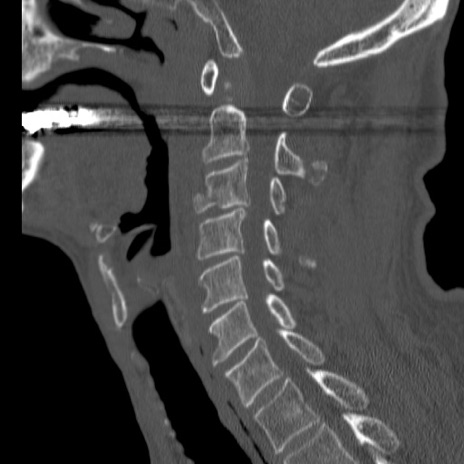

症例46 頚椎CT(矢状断像)

【症例】80歳代男性

【主訴】両側頚部〜上肢のしびれ

【現病歴】昨日、自宅内で転倒、その後より上記症状あり。意識障害なし。

【身体所見】両側上肢のallodynia(熱痛覚過敏)あり。MMTおよびDTRは正確な所見取れず。両上肢の挙上はなんとか可能。

異常所見と診断は?